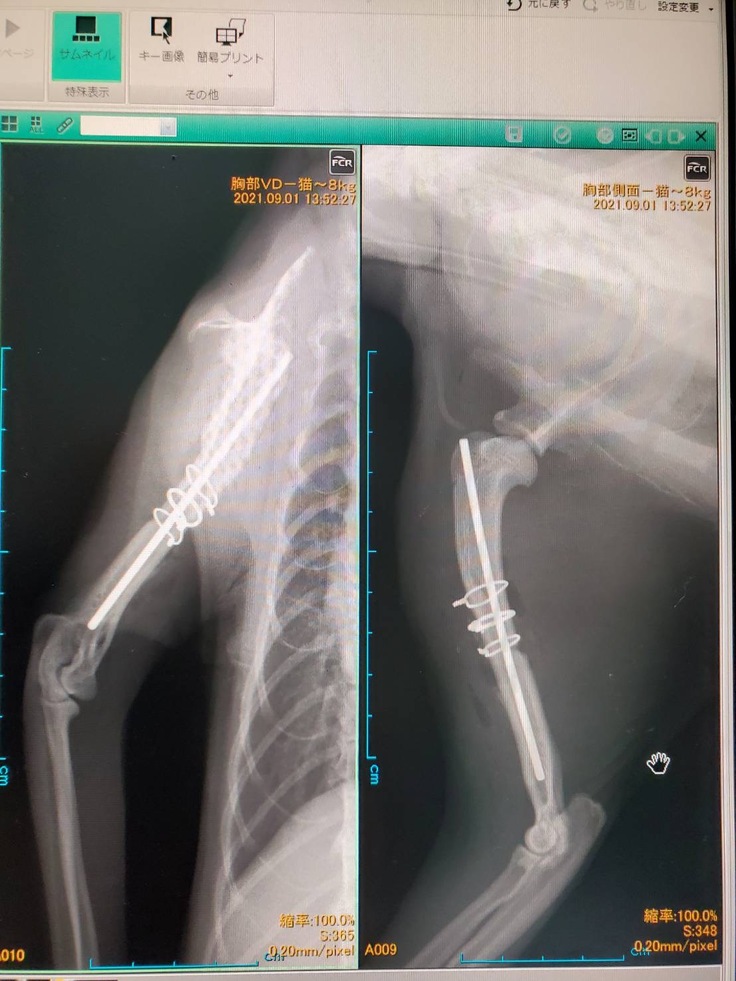

9/1無事手術を終えました。

術後、獣医さんの話を伺いまして、骨折した箇所を開いたところ、状態があまり良くなく、最低でも1週間、場合によっては2週間以上の入院が必要で現在入院中です。

現段階ではわかりませんが、麻痺が残る事もあるそうなので、その際は獣医師と相談しながら今後の治療とリハビリを行います。